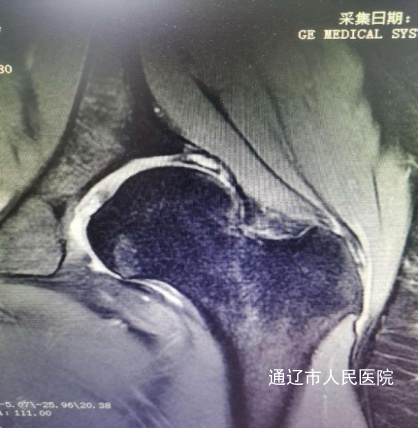

术前影像:

患者张某,女性,24岁,2年前开始出现左侧髋关节肿痛伴活动受限,严重影响日常生活,门诊经过查体及髋关节半髋磁共振检查诊断为:髋臼撞击综合征合并盂唇撕裂。由于患者年纪较轻,左侧髋关节撞击导致髋臼盂唇损伤,长期疼痛,胡中申主任医师带领其关节外科团队对该病例进行详细周全地讨论,综合评估患者病情并得到家属同意后,建议实施髋关节镜手术治疗。